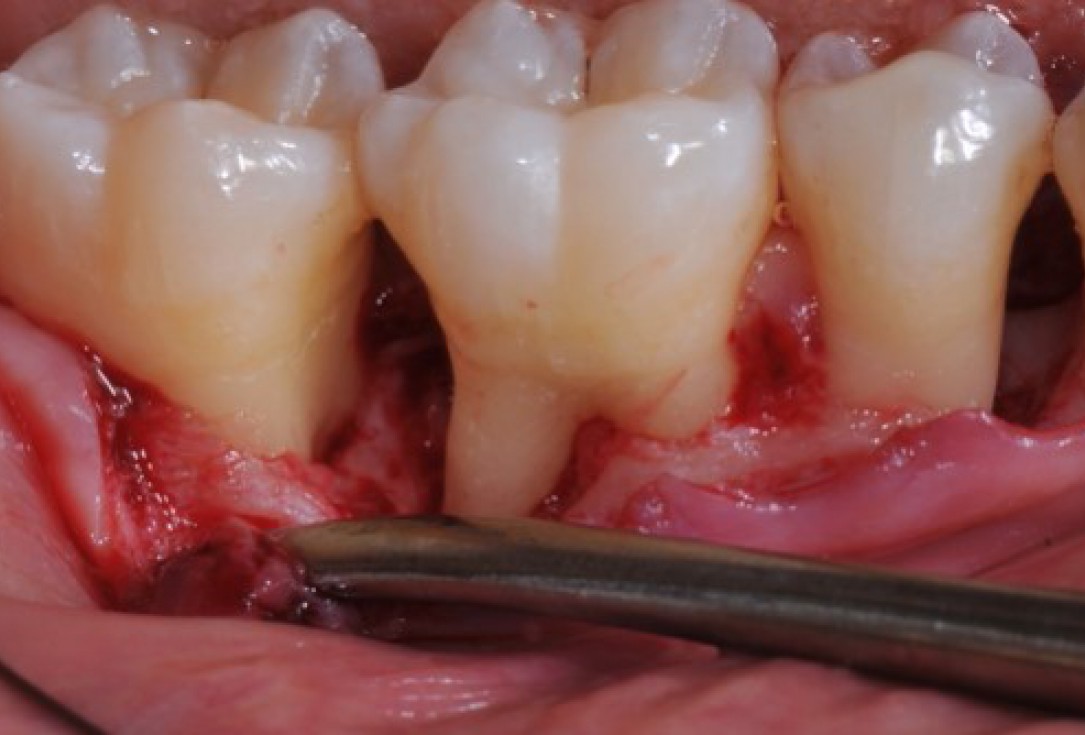

Radiographic view before periodontal regenerative therapy with Straumann® Emdogain®. A deep intrabony defect appeared mesially and distally on the left mandibular first premolar. Pre-surgical probing measured 8 mm. The defect morphology presented as well-contained.